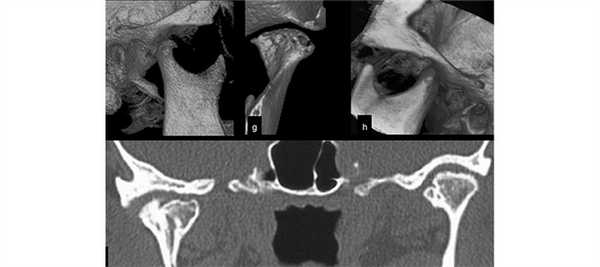

(Слева) При аксиальной КТ в костном окне определяется расширение суставного пространства правого височно-нижнечелюстного сустава, также видны множественные эрозии округлой формы в прилежащих отделах основания черепа с поражением скуловой дуги и большого крыла клиновидной кости выше наружного края овального отверстия.

(Справа) При МРТ Т1ВИ в корональной проекции визуализируется гипоинтенсивное объемное образование правого ВНЧС с «ободком» низкой сигнальной интенсивноаи. Также визуализируется гипоинтенсивное экстрааксиальное объемное образование в средней черепной ямке, тесно прилежащее к интракраниальным структурам, с таким же гипоинтенсивным «ободком» по периферии.

(Справа) При МРТ Т1ВИ в корональной проекции визуализируется гипоинтенсивное объемное образование правого ВНЧС с «ободком» низкой сигнальной интенсивноаи. Также визуализируется гипоинтенсивное экстрааксиальное объемное образование в средней черепной ямке, тесно прилежащее к интракраниальным структурам, с таким же гипоинтенсивным «ободком» по периферии. (Слева) При MPT T1BИ FS с КУ в аксиальной проекции, выполненной пациенту с пигментным ворсинчато-узелковым синовитом (ПВУС), в расширенном суставном пространстве правого ВНЧС и вокруг него визуализируются многочисленные узлы с гипоинтенсивным сигналом. Обратите внимание, что контрстаное усиление выражено минимально.

(Слева) На аксиальной КТ в костном окне определяется расширение суставного пространства правого ВНЧС с наличием множественных округлых эрозий прилежащих отделов основания черепа с вовлечением внутреннего края скуловой дуги и большого крыла клиновидной кости вплоть до наружного края овального отверстия.

(Справа) На корональной МРТ (Т1 ВИ) определяется гипоинтенсивное объемное образование В правого ВНЧС с «ободком» на периферии еще более низкой интенсивности, продолжающееся во внемозговое объемное образование средней черепной ямки с похожим ги-поинтенсивным «ободком» на периферии.